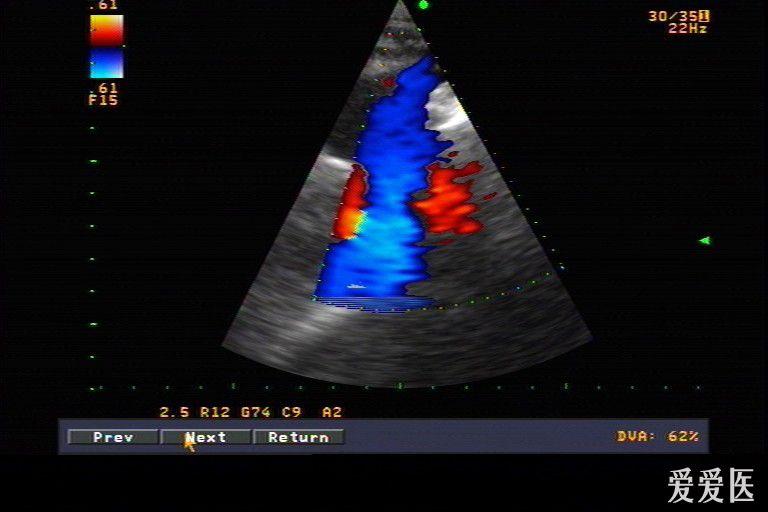

症和右室双出口超声检查中国专家共识(2022版)(二)_动脉_进行_分型